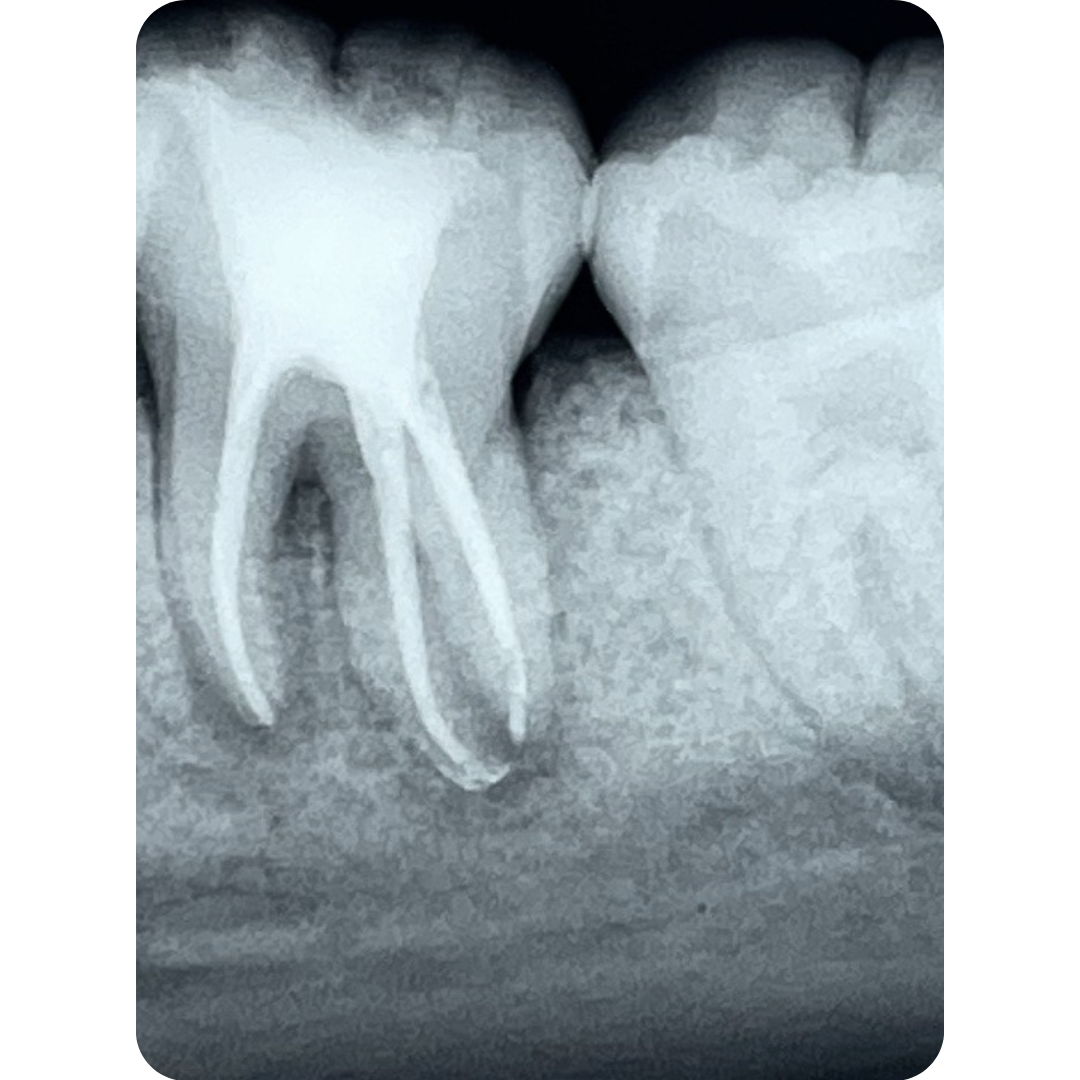

Tratamento com agentes bioativos para estimulação da formação radicular antes da obturação.

*Imagens clínicas e radiográficas documentadas podem ser apresentadas em consulta, respeitando o sigilo e ética profissional.

Retratamento endodôntico

Com atuação marcada pela excelência técnica, atende casos de alta complexidade com foco em eficiência, controle da dor e resultados previsíveis. Mais de 60% dos seus atendimentos são retratamentos — casos em que o primeiro tratamento de canal falhou e exige um nível mais alto de intervenção.